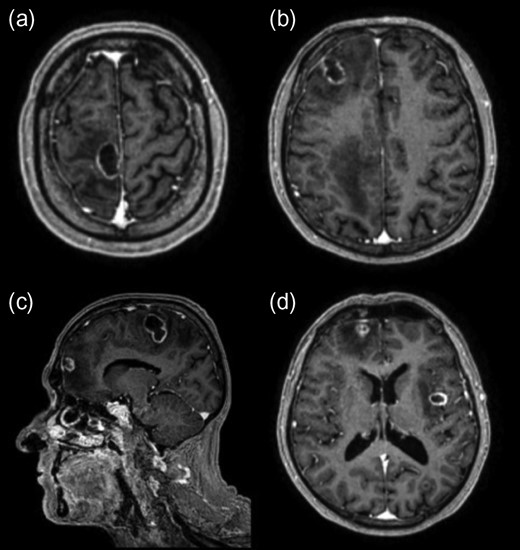

A CT brain revealed a right frontal mass lesion with surrounding oedema which was concerning for malignancy when taken in conjunction with the weight loss. Investigations for a primary tumour were negative including a CT of the chest, abdomen and pelvis in addition to upper GI endoscopy. Tumour markers did not reveal any abnormality. Additional testing for immunocompromise including HIV was negative and no primary source of infection was identified. A subsequent MRI brain revealed a total of five ring-enhancing lesions with vasogenic oedema distributed throughout both cerebral hemispheres with the largest measuring >2 cm (Fig. 1).

Initial post-contrast T1-weighted MRI demonstrating three lesions involving the right frontal lobe (a, b, c) with another in the left lateral occipital lobe (d) and one in the left insular region (d). The lesions also displayed complex walls typical of an abscess capsule on T2-weighted imaging and demonstrated central diffusion restriction (not shown).